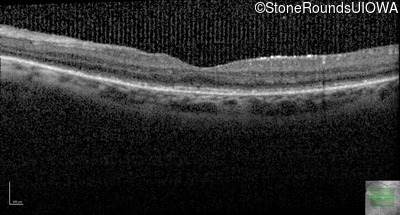

Optical Coherence Tomography - Right - 20/50 +1

Exemplar / OCT Stack